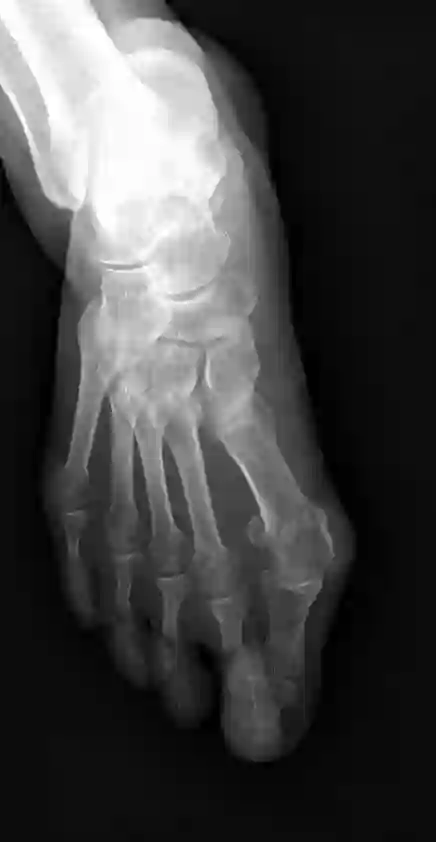

Angular measurements is essential to make a resonable treatment for Hallux valgus (HV), a common forefoot deformity. However, it still depends on manual labeling and measurement, which is time-consuming and sometimes unreliable. Automating this process is a thing of concern. However, it lack of dataset and the keypoints based method which made a great success in pose estimation is not suitable for this field.To solve the problems, we made a dataset and developed an algorithm based on deep learning and linear regression. It shows great fitting ability to the ground truth.